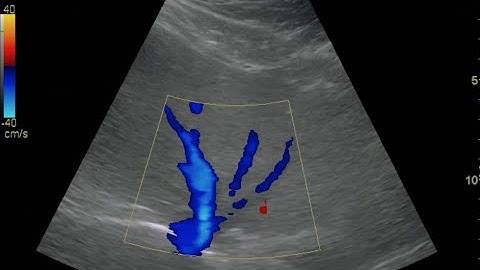

How to... Obtain a Hepatic Vein Waveform